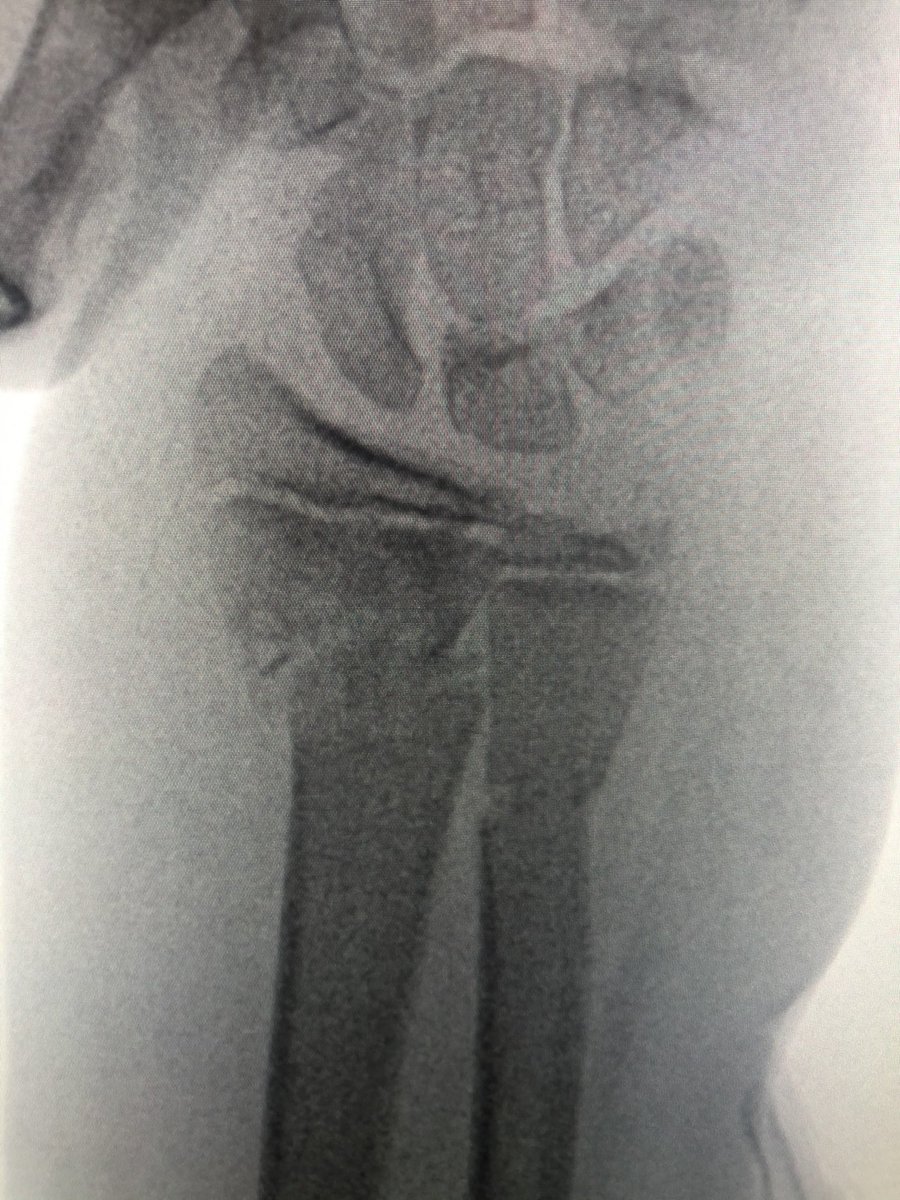

[3/4] This is my reduction, manually on distal fragment, with my other hand on threaded wire pulling it radially, using it as joystick. Once lined up, since distal wire already in and pointing in correct direction, all my resident has to do is fire wire into proximal fragment.